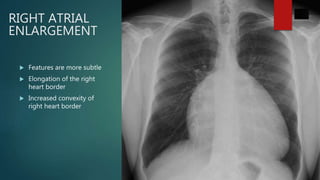

RIGHT ATRIAL

ENLARGEMENT

 Features are more subtle

 Elongation of the right

heart border

 Increased convexity of

right heart border

RIGHT ATRIAL ENLARGEMENT  Featuresare more subtle  Elongation of the right heart border  Increased convexity of right heart border